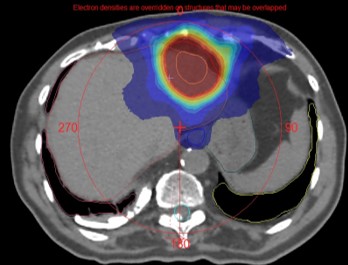

SBRT has been defined by the American College of Radiology (ACR) and the American Society for Radiation Oncology (ASTRO) as the use of very large radiation doses, defined as >6 Gy/fraction delivered in a few (five or fewer) fractions. SBRT has unique radiobiological characteristics that can cause dramatic tumor response, leading to the associated term “ablative” radiation therapy. SBRT requires precise localization of the target volume. “Stereotactic” refers to the fact that SBRT is centered on the target volume and uses online IGRT to localize the tumor in space. The irradiated tissue volume is minimal to reduce toxicity, with a high dose gradient, high conformality, and heterogeneous dose distribution in the PTV. The techniques used can be coplanar or non-coplanar, with IMRT, arc therapy, or cones. The margins are small, dosimetry and dose delivery are complex, and require precise small-field dosimetry.

SABR/SBRT is used with high local control and excellent tolerance to treat primary tumours instead of surgery: lung, prostate, pancreas, liver Hepatocellular Carcinomas, Cholangiocarcinomas, Renal cancer…